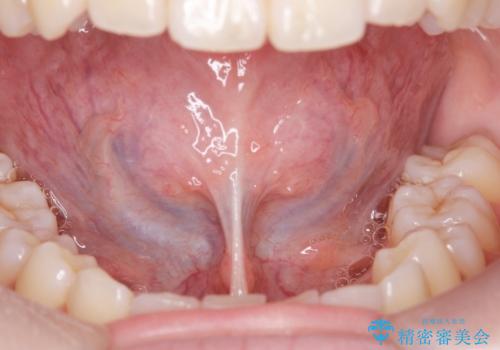

舌小帯の形成手術を行うことにより舌が口蓋に届くようになり

ら行が言いやすくなりました。